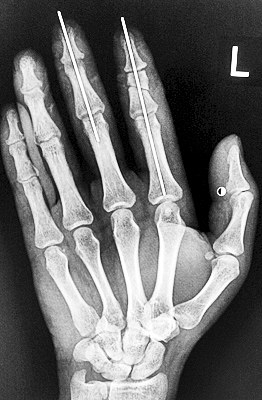

術(shù)后X光顯示,骨骼對(duì)位良好。

最終,盧微波和團(tuán)隊(duì)找好了需要的血管和神經(jīng),做好標(biāo)記后,開(kāi)始固定食指骨骼、吻合肌腱,最后在顯微鏡下用直徑20微米的無(wú)創(chuàng)顯微縫合線開(kāi)始吻合血管和神經(jīng)。

在經(jīng)過(guò)兩個(gè)多小時(shí)手術(shù)后,早上8時(shí)許,盧微波下令松止血帶,數(shù)十秒后男子蒼白的食指逐漸紅潤(rùn)起來(lái),食指在離體10個(gè)小時(shí)后恢復(fù)血運(yùn)。

緊接著,盧微波又開(kāi)始中指再植手術(shù)。上午10時(shí)許,中指在離體12小時(shí)后也成功恢復(fù)血運(yùn)。